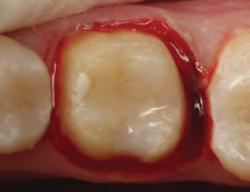

1. Subgingival preparation with bleeding. BLEEDING HEMOSTASIS

2. Scrub Astringedent™ X hemostatic firmly against bleeding tissues with Metal DentoInfusor™ tip.

CLEANING/TESTINGDISPLACEMENT

3. Firm air/water spray removes residual

and tests tissue for quality, profound hemostasis.

Remove

4. Soak Ultrapak™ knitted cord in Astringedent™ X hemostatic, pack, and leave for 5 minutes.